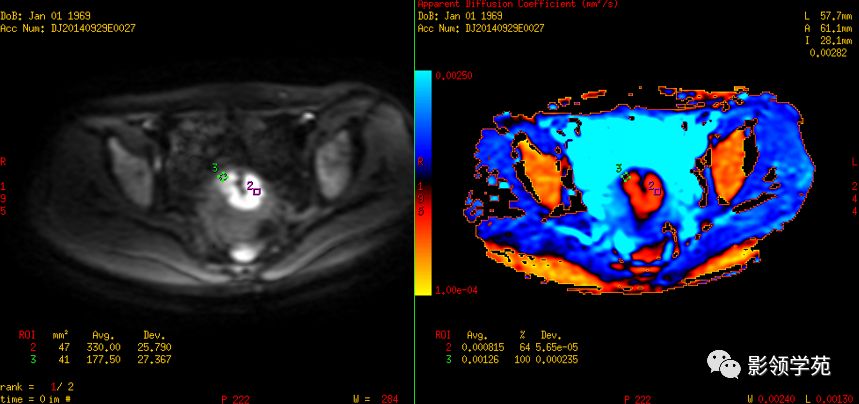

磁共振扩散加权成像,DWI

DWI是目前唯一能在活体观察组织水分子微观运动的无创性影像学方法,可以检测出与组织含水量变化相关的形态学和生理学早期改变,并以表观扩散系数(ADC)值来量化表示。

DWI:局限性高信号,癌组织ADC值<癌旁组织<小于正常宫颈组织

宫颈癌术后复发患者,DWI上病灶较T2 fs及T1+C更加明显